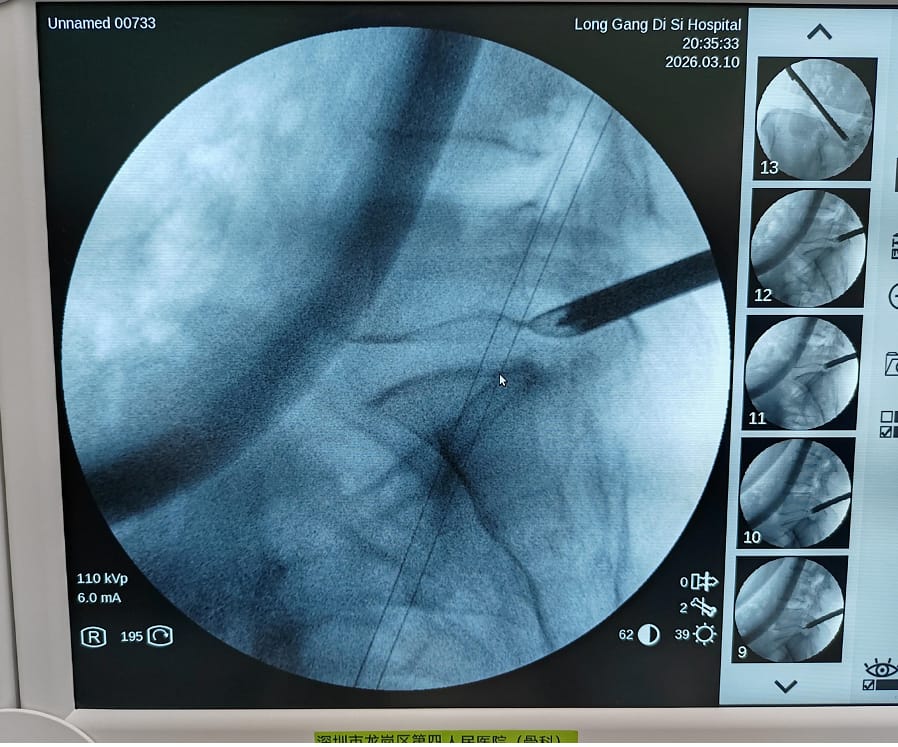

手術由骨科主任盧鎮生主任醫師主刀。術中僅在患者腰部作一約0.5-1厘米的小切口,藉助椎間孔鏡系統,在高清視野下精準定位並摘除突出的椎間盤組織,全程出血少、創傷小。術後患者腰部及左下肢疼痛、麻木症狀迅速緩解,恢復情況良好,第二天即可自主下床活動,患者及家屬對治療效果表示高度滿意。

椎間孔鏡是一種先進的微創內窺鏡設備,通過腰部微小切口進入椎間孔區域,醫生可在顯示屏上清晰觀察突出的椎間盤及神經組織,實現精準操作。